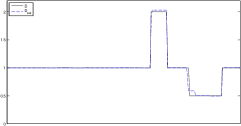

In this section, the proposed algorithm is tested on two sets of simulated two-dimensional data (with different parameter range and level of detail). We also vary the noise on the data since the reconstruction quality strongly depends on the noise level.

The data (see Figures 1 and 2) was generated in the diffusion model (1.2) using self-written (linear-basis) finite element code in MATLAB. For both examples, we took and used a uniform boundary condition . The simulated data were generated on a -grid and then down-sampled (by averaging) to to avoid inverse crime. After that, Gaussian noise with different intensities (standard deviations of and of the average signal value ) was added to the data.

The edge detector is used to detect jumps in the derivatives of the data up to second order (to obtain an initial estimate of the parameter jump set ). Since this process is highly sensitive with respect to noise, we varied the edge detection procedure subject to the amount of noise in the data. In the noise-free examples, we estimated the jumps of all three functions , that is, jumps of derivatives of up to second order. We restricted the jump estimation to for the low-noise examples (i.e., jumps of derivatives up to first order) and in the high-noise examples (only jumps in the data itself).

Reconstruction results and error profiles at different noise levels can be seen in Figures 3 and 4. In both examples, the noise-free reconstructions are very accurate and contain mostly smoothing error. In the low-noise reconstructions, due to the fact that more regularization is necessary, some of the parameter variation is underestimated. In the high-noise examples, most detail in is lost since a lot of regularization is required to get reasonable results. The fine detail in can, however, still be recovered very accurately in both examples.